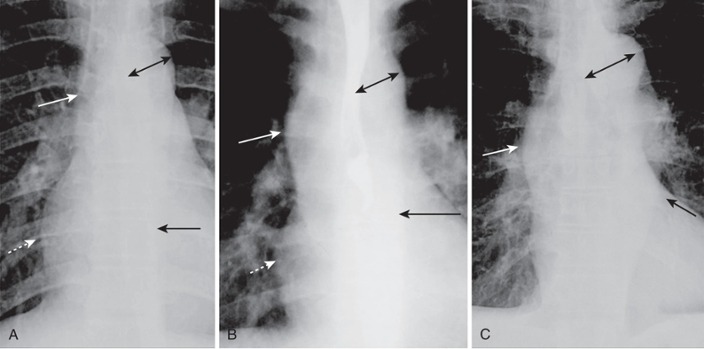

Aortic Contours

Normal

The ascending aorta is a low-density, almost straight edge (solid white arrow)

Does not project beyond the right heart border (dotted white arrow).

The aortic knob is not enlarged (double arrow)

The descending aorta (solid black arrow) almost disappears with the shadow of the thoracic spine

Aortic stenosis

The ascending aorta is abnormal as it projects convex outward (solid white arrow) almost as far as the right heart border (dotted white arrow)

This is secondary to post-stenotic dilatation

The aortic knob (double arrow) and descending aorta (solid black arrow) remain normal.

Systemic hypertension

Both the ascending (solid white arrow) and descending aorta (solid black arrow) project too far to the right and left, respectively

The aortic knob is enlarged (double black arrow)